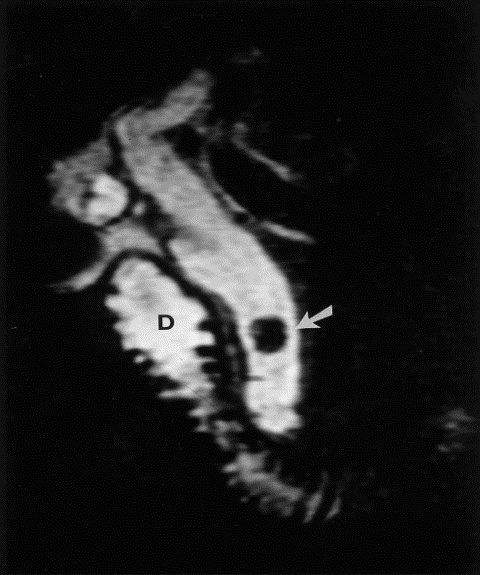

Hình 7. Hình ảnh sỏi đường mật trên phim MRI [5]